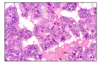

follicular carcinoma

follicular carcinoma

2nd ost common form of thyroid ca

slowly enlarging painless nodule

more common in areas w iodine deficiency

range from encapsulated to widely invasive tumors with necrosis and hemorrhgage

lower survival (age, size, invasion, metastasis)